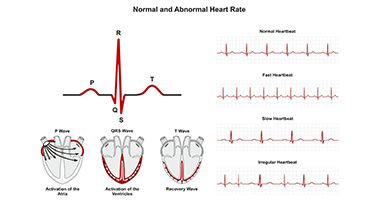

Normal Heart Rate in Adults and Kids: When Is It Dangerous?

The number of times your heart beats in a minute determines your heart rate. Your heart rate keeps fluctuating to some extent throughout the day. It varies according to the activities you do.

Irregular Heartbeat: Causes and Treatment for Heart Arrhythmia

An arrhythmia is an abnormal heartbeat. This signifies that your heart is not in its normal rhythm. Arrhythmias affect approximately 1.5% to 5% of the population. It could feel like your heart missed a beat, added one, or is "fluttering." It may feel like it's beating too quickly (tachycardia) or too slowly (bradycardia). Some patients may not notice anything.

Tachycardia (Fast Heart Rate): Symptoms, Causes And Treatment

A fast heart rate, medically termed as tachycardia, can be an alarming condition if left unchecked. It occurs when the heart beats faster than normal, typically over 100 beats per minute (BPM) in adults while at rest. While occasional increases in heart rate during exercise or stress are normal, persistent tachycardia might indicate an underlying health issue. This blog aims to discuss what is tachycardia, its symptoms, causes, and treatment options while addressing concerns like “what is a dangerous heart rate” and “the reason for high pulse rate.”

Monitoring Your Heart Rate: What Does It Say?

Heart health is fundamental to overall wellness since the heart plays an essential function in supplying oxygen and nutrients to all parts of the body. Monitoring heart rate can provide invaluable insights into cardiovascular health and help detect potential problems early on.Understanding normal heart rates and how they vary with age, fitness, and lifestyle can help you take proactive steps toward heart health.

Normal Heart Rate in Adults and Kids: When It's Dangerous?

Read this blog to learn about the normal heart rate in adults and children, the causes of normal fluctuations, and when an abnormal rate is dangerous.